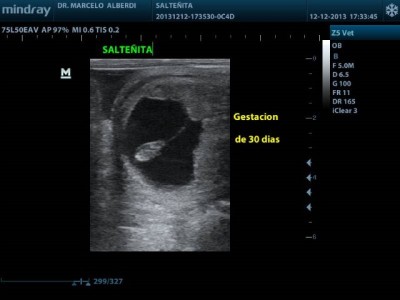

Ecografía

Inicialmente se comenzó a utilizar en reproducción para el diagnóstico de gestación en la Yegua, permitiendo reducir las gestaciones de mellizos, gran avance en la reproducción.

En reproducción actualmente nos permite la evaluación del aparato reproductivo del Padrillo y la Yegua, cómo la determinación del sexo fetal a partir del día 56 de gestación en adelante.

Disponemos de dos ecógrafos de última generación,con alta calidad de imágen(Doppler Color pulsado), con diferentes sondas para cada región, esto nos permite certeza en el diagnóstico y tratamiento.